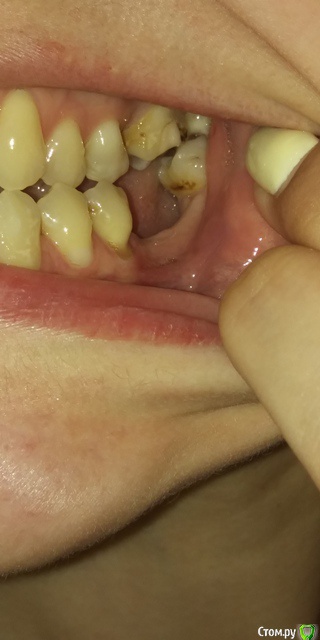

Есть рецессии на нижних зубах и на верхнем клыке слева и резорбция. Ортодонты говорят, что это последствия неправильного прикуса, травмирующего смыкания и с брекетами все стабилизируется, но из-за движения зубов может и усугубиться, как повезет. Вестибулопластику никто не предлагал, а один вообще сказал, что в моем случае она бесполезна. У хирурга-парадонтолога другое мнение: нужно сделать сначала операцию на нижних зубах (углубить преддверие, устранить тяжи и положить какой-то там замещающий материал), а потом поставить брекеты, иначе без операции брекеты спровоцируют еще большее оголение и рецессии станут просто огромными.  А после брекетов уже закрывать, если нужно, рецессии.  Прошу поделиться вашим мнением? В чем причина рецессий и резорбции? Поможет ли в моем случае вестибулопластика?